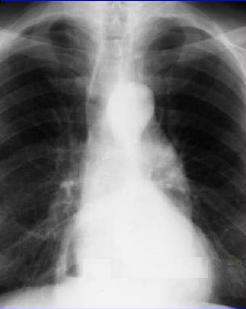

Une autre cas de hernie

hiatale avec image hydro-areique a droit |